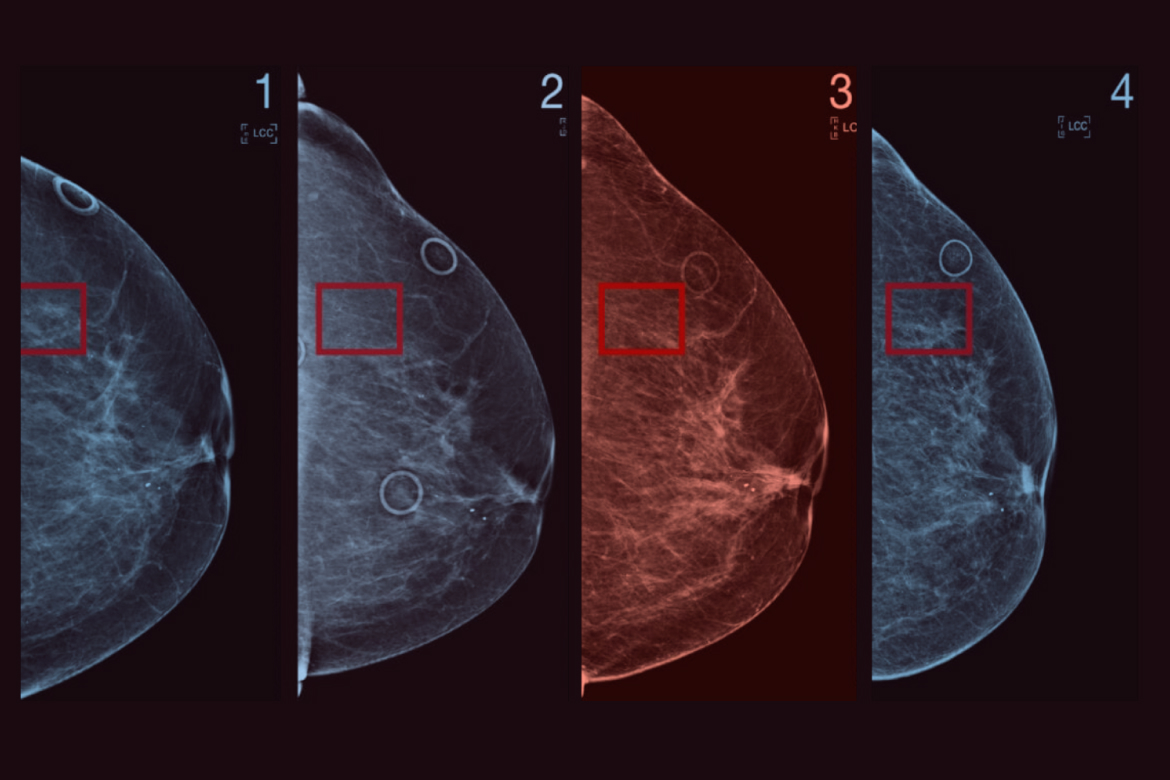

A significant hurdle in mass screening programs is the radiographic appearance of the breast parenchyma itself, which often mimics the very pathology being sought. “The inherent limitations of conventional mammography—most notably its reduced sensitivity in women with dense breast tissue” underscores a major clinical and technological bottleneck. Dense breasts, characterized by a higher proportion of fibroglandular tissue relative to fat, appear white on a mammogram. Since cancerous tumors also manifest as white densities, the malignancy can be effectively camouflaged, a phenomenon often described as “masking.” Digital Breast Tomosynthesis (DBT), frequently referred to as 3D mammography, emerged as the first widely adopted answer to this problem. By capturing a series of low-dose X-ray images from different angles and reconstructing them into a three-dimensional volume, DBT allows the radiologist to scroll through thin slices of breast tissue, dramatically reducing the effect of overlapping structures that obscure small cancers in dense breasts.

Digital Breast Tomosynthesis represents a fundamental upgrade to the anatomical visualization capabilities of X-ray-based imaging. “By capturing a series of low-dose X-ray images from different angles and reconstructing them into a three-dimensional volume” describes the core technical mechanism that has improved cancer detection rates, particularly for smaller, invasive tumors. While DBT has significantly lowered recall rates and increased the detection of invasive cancers compared to standard 2D digital mammography, it still relies on morphology—the shape and structure of the tissue—for diagnosis. This is where functional imaging modalities come into play, offering a physiological view of the tissue by assessing blood flow and metabolic activity, which are fundamentally altered in malignancy. Techniques such as Contrast-Enhanced Mammography (CEM) and Molecular Breast Imaging (MBI) are gaining traction by exploiting the increased vascularity and high metabolic demand of growing tumors.